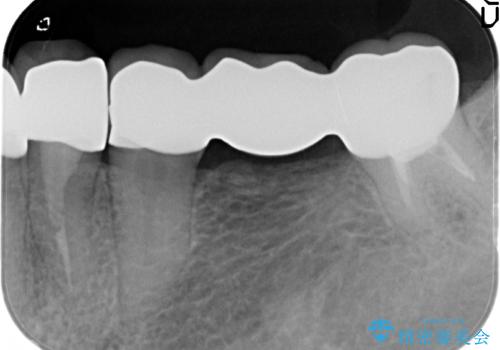

精度の高いジルコニアブリッジの製作に加え歯茎にぴったりとそわせたオベイトポンティック形態とすることで清掃性・審美性に優れたブリッジを製作します。

歯ぐきの形態にそわせ、凸型でくぼみのないオベイト型のポンティックはプラークの溜まりにくく審美性も達成できるポンティック形態です。